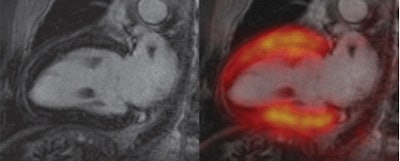

Two-chamber views show "stunned myocardium" in a 66-year-old patient with ST-elevation myocardial infarction and acute occlusion of the left anterior descending artery. Cardiac PET/MRI was performed seven days after intervention. Late gadolinium-enhanced image (top left) shows no infarction zone. Fused late gadolinium-enhanced and PET images (top right) show that tracer uptake was reduced in segments 13-15 and 17. T2-weighted MR image (bottom left) shows myocardial edema (arrows) that corresponded well with the area of reduced tracer uptake on the bottom right image. All images courtesy of Radiology.